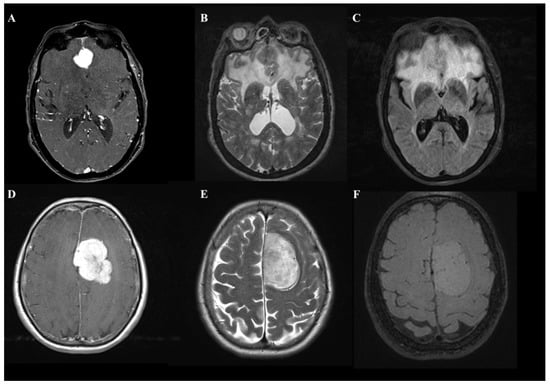

Meningiomas are benign neoplasms arising from meningoendothelial cells [1]. They are the most frequent intracranial tumor in the adult population. Although intracranial meningiomas (IM) are typical extra-axial tumors, the occurrence of peritumoral brain edemas (PBE) are not rare, affecting between 38% to 67% of IM patients [1,2,3]. It is well recognized that a large proportion of PBE can increase morbidity and mortality [2] and determine brain displacement, increase intracranial pressure [3], and add the risk of perioperative seizures [4]. In daily clinical practice, it is not uncommon for a neurosurgeon to confront the diagnosis of an IM with a large proportion of edema irrespective of the site and size of the contrast-enhancing lesion (Figure 1).

Figure 1.

A comparison of two cases of patients with frontal lobe meningioma with an asymptomatic onset that, on MRI images, document entirely different volumes of edema. In the first case, T1-weighted with MDC (A), T2-weighted (B), and FLAIR (C) images show a 2 cm para-alpine lesion with edema involving the entire frontal lobe. In the second case, the identical sequences (D–F) show a more than 4.5 cm lesion in diameter with a volume of edema almost absent.